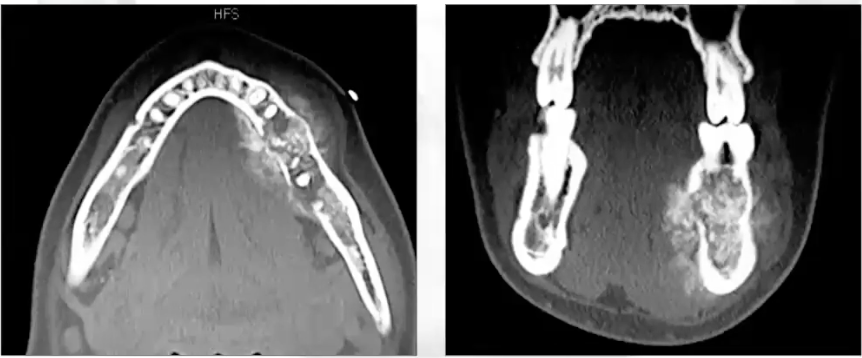

What is this image showing?

Bone destruction seen in osteosarcoma - cortical plate is destroyed